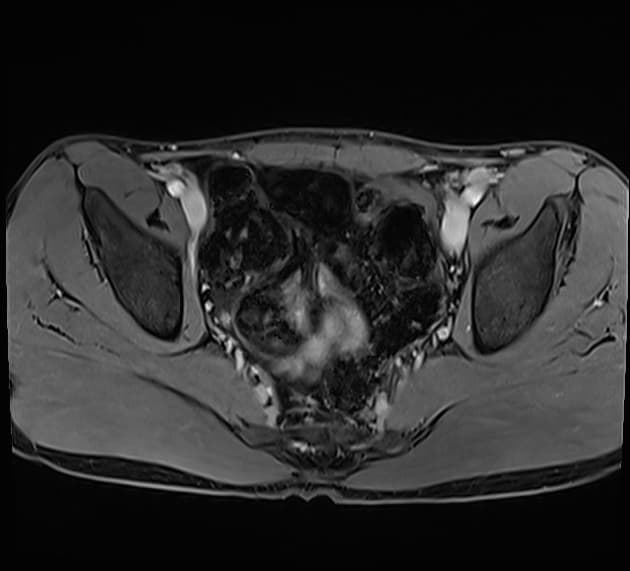

Axial T2

MRI•Axial T2•1 Img

- Khối dạng nang (cystic mass) nằm ở vùng ngoại vi tuyến tiền liệt (peripheral prostate gland), phần trung tâm (center portion), có vẻ như không thông với niệu đạo tiền liệt tuyến (non communicating with the prostatic urethra).

Nang trong tuyến tiền liệt (intraprostatic cyst): có khả năng là nang ống Mullerian (probable Mullerian duct cyst).

Nang ống Mullerian là di tích bẩm sinh của ống Mullerian không thoái triển ở nam giới. Những nang này thường nằm ở đường giữa, phía sau niệu đạo tiền liệt tuyến và phía trên gò tinh (verumontanum). Một đặc điểm chẩn đoán quan trọng là chúng thường không thông với niệu đạo, giúp phân biệt với nang túi bầu dục tuyến tiền liệt. Về mặt lâm sàng, chúng có thể không có triệu chứng hoặc biểu hiện ở độ tuổi 30-40 với các triệu chứng như xuất tinh máu, đau vùng chậu hoặc tắc nghẽn đường tiểu. Trên chẩn đoán hình ảnh (siêu âm, CT hoặc MRI), chúng xuất hiện dưới dạng cấu trúc chứa dịch đơn thuần hoặc phức tạp mở rộng lên trên tuyến tiền liệt.